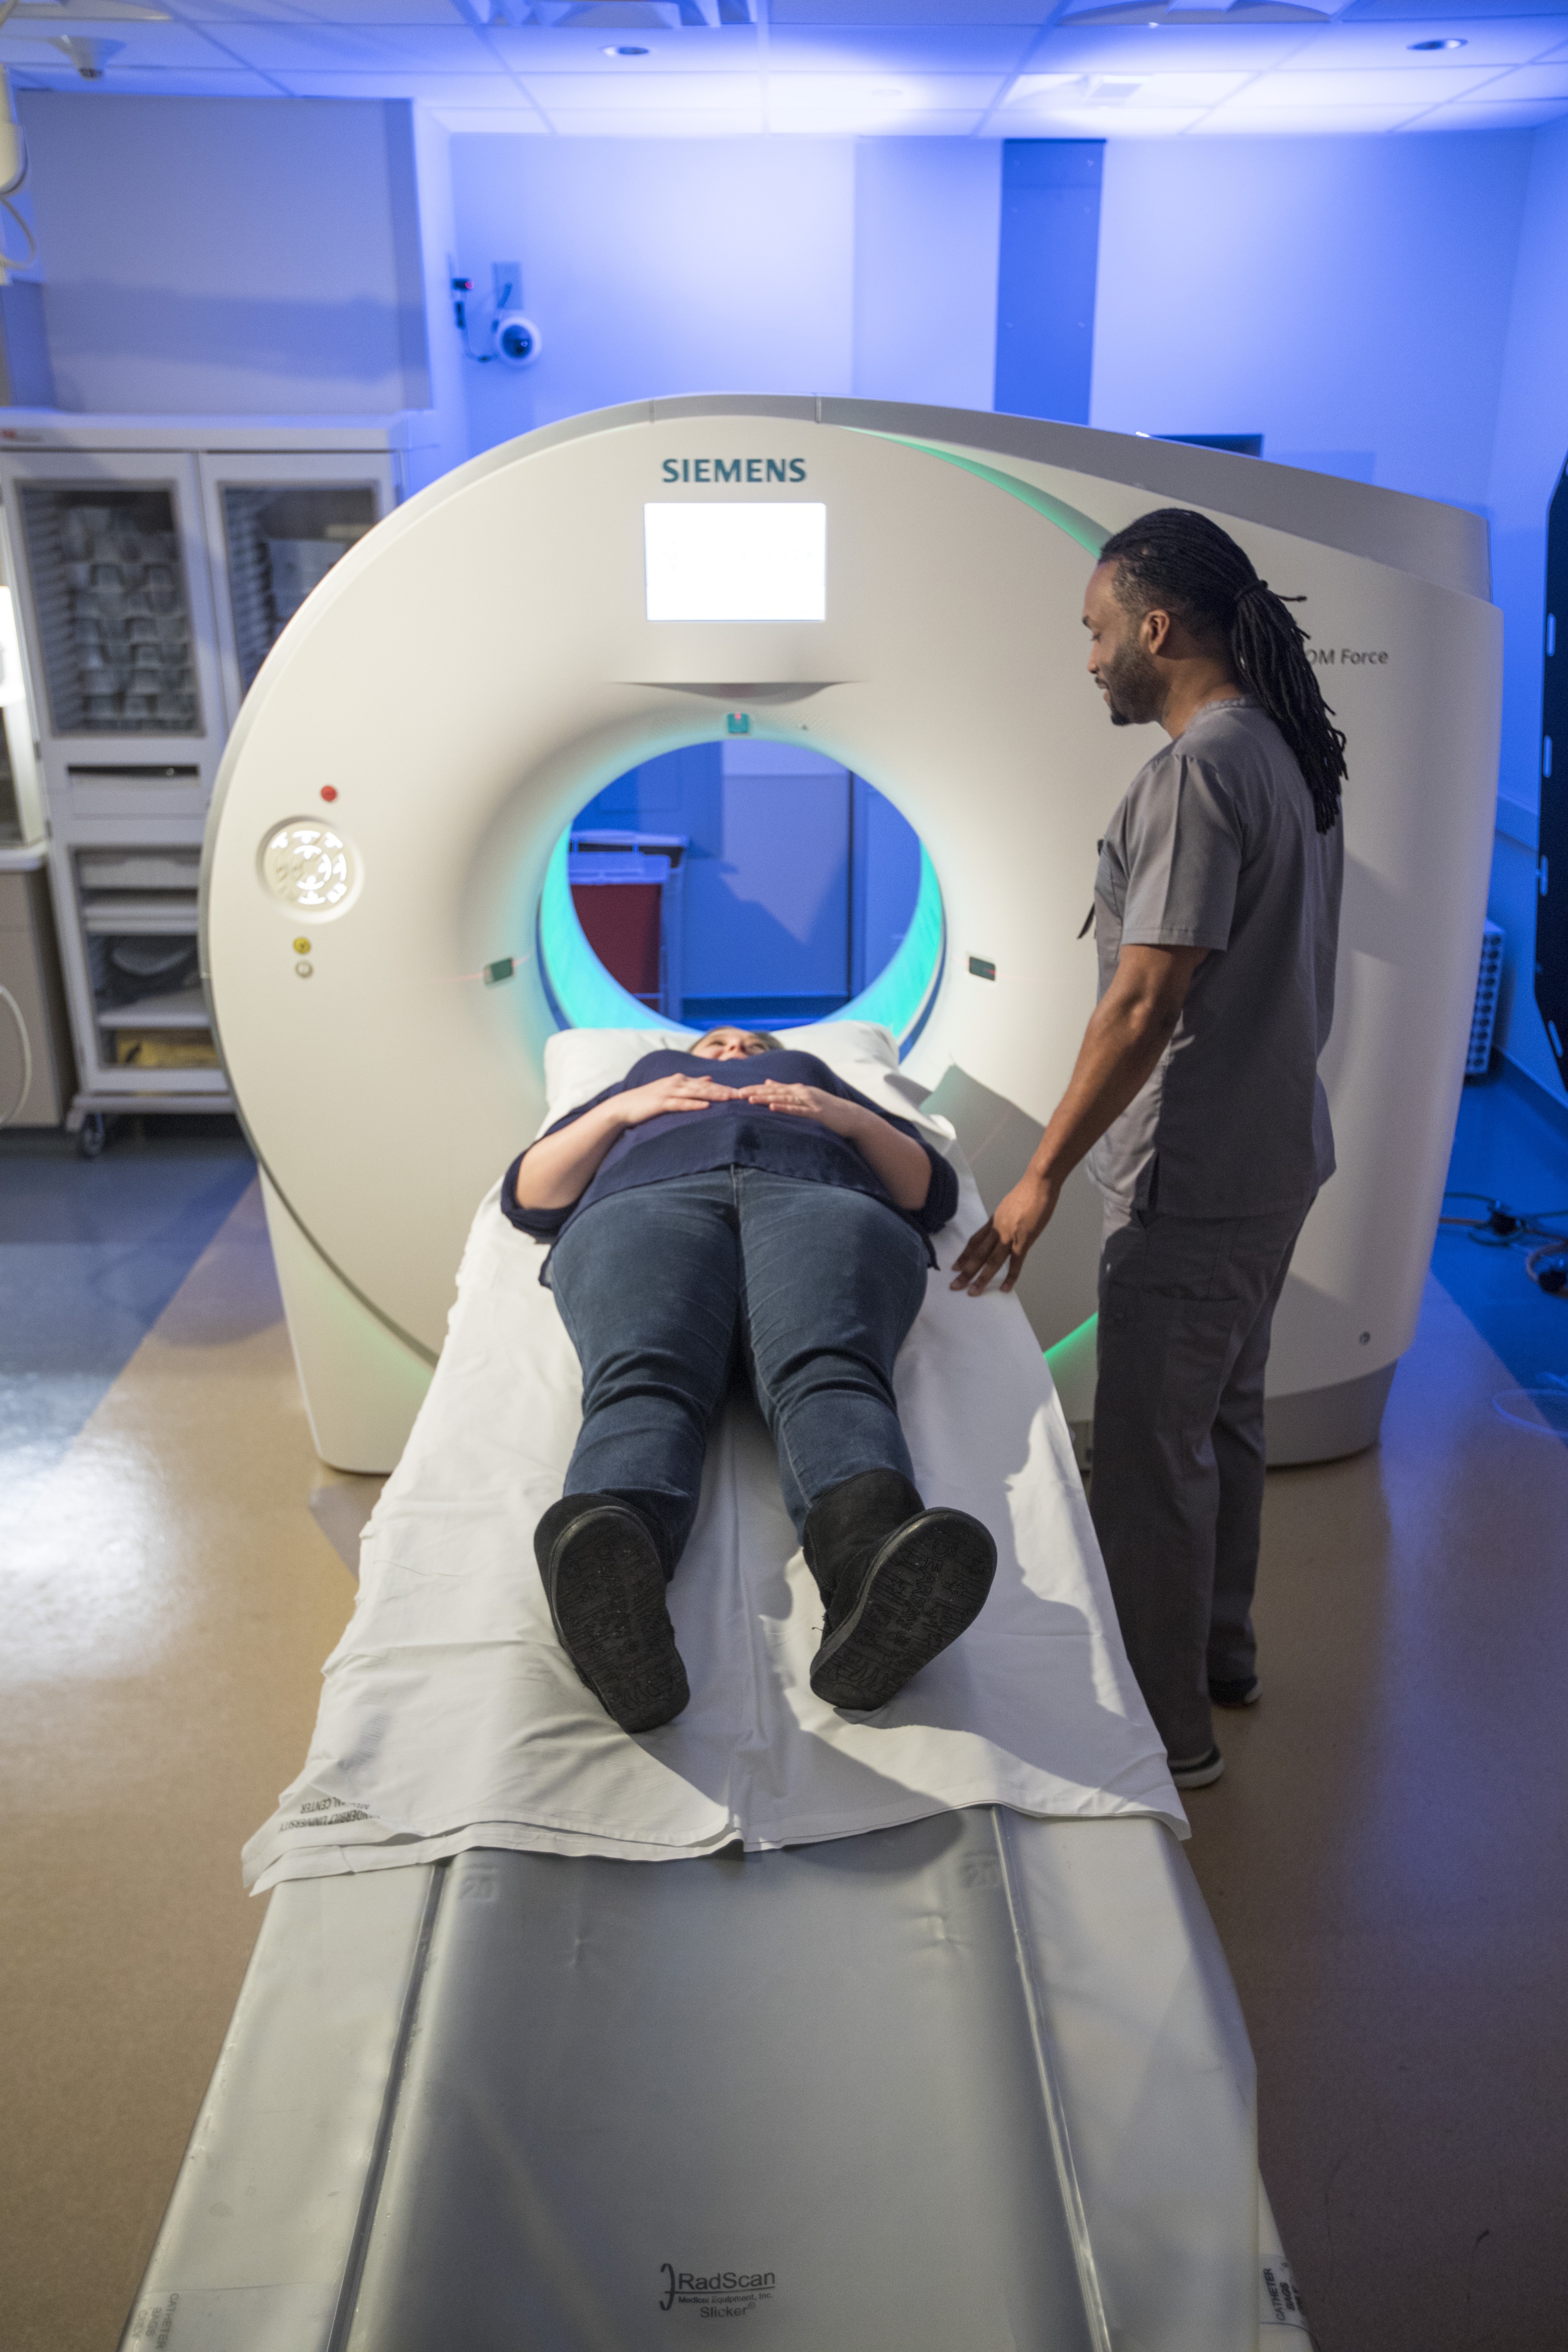

The Department of Radiology recently completed installation of two new, next generation computed tomography (CT) scanners in the Vanderbilt University Medical Center (VUMC) hospital and emergency department.

The Department of Radiology recently completed installation of two new, next generation computed tomography (CT) scanners in the Vanderbilt University Medical Center (VUMC) hospital and emergency department.

The first clinically operational in Tennessee, the Siemens Somatom Force CT scanners can create 384 slices per rotation, freeze motion in a beating heart, scan an entire patient from head-to-toe in under two seconds and image with multiple energies.

“These new super-fast CT units are a great benefit to patients and the professionals who operate them,” said Rich Pierce, Chief of Finance and Administration, Department of Radiology. “Worrying about a health concern that requires a diagnostic CT is never pleasant. Providing fast and precise imaging will help ease the burden.”

The dual-source, dual energy, wide detector CT systems reduce the radiation exposure and require lower amounts of intravenous contrast while producing higher quality exams. The Force CT scanner effectively contains two scanners in the same enclosure, which allows unparalleled options for completing an exam. One rotation of the gantry takes 0.25 seconds and each image has a temporal resolution of 66-msec.

“These new capabilities enhance the images we can produce, the types of studies we can perform and improve the care we provide to each and every patient,” said Dr. Carr. “The scanners will support the care of all patients by providing the most advanced imaging with the lowest possible exposure to X-rays and reduced intravenous contrast media.”